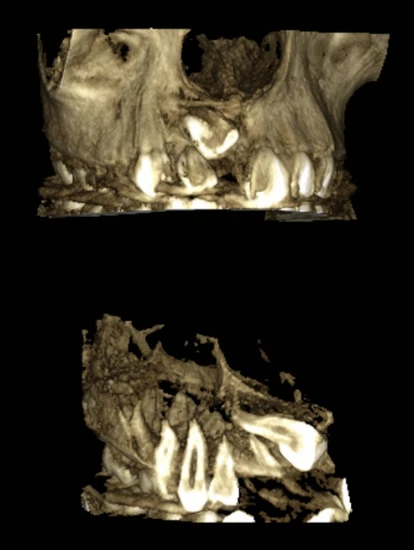

בבדיקה הקלינית והדימותית נמצא כי שן 11 הייתה כלואה בעמדה הוריזונטלית חריגה, מעל שורשי החותכת הלטרלית והניב, עם מורפולוגיית שורש אבנורמלית ועם הפרעה ממשית לבקיעה התקינה של שיניים 12 ו 13, שכבר הראו הטיה משמעותית. בגיל זה לא ניתן היה לשקול שתל כפתרון חלופי, אך גם השארת השן הכלואה במקומה לא הייתה אפשרית, משום שהיא חסמה את התפתחות ובקיעת השיניים הסמוכות ופגעה במבנה התקין של הקשת המתפתחת.

הטיפול החל בהדבקת סמכים ובפתיחת מקום מדויקת לשן הכלואה. לאחר מכן בוצע תכנון כירורגי קפדני על בסיס CT תלת מימדי, כדי להבין באופן מלא את מנח השן, את צורת השורש ואת יחסיה לשיניים הסמוכות. החשיפה בוצעה אצלנו במסגרת המרכז לשיניים כלואות, בשיתוף עם ד"ר טלי שקרצ'י, מומחית לניתוחי חניכיים, תוך בחירה בחשיפה סגורה. בגישה זו, לאחר חשיפת השן והדבקת כפתור זהב, החניכיים נתפרו חזרה למקומם, כך שהריפוי התבצע בצורה מלאה ומבוקרת. מטרת הגישה הייתה לדמות בקיעה טבעית ככל האפשר, ולאפשר בהמשך לא רק את הבאת השן לקשת, אלא גם קבלת מורפולוגיית חניכיים תקינה, בריאה ואסתטית.

כאן בדיוק התחיל האתגר האמיתי. בשל העמדה המורכבת של השן וצורת השורש החריגה, לא ניתן היה פשוט למשוך אותה למקומה. היה צורך לבצע תחילה משיכה מבוקרת לכיוון מיזיאלי, אל קו האמצע, ורק לאחר מכן לבצע שליטה מדויקת בשורש באמצעות טורק, עד להבאת השן לעמדה התקינה בקשת. זהו מהלך שדרש הבנה עמוקה של ביומכניקה אורתודונטית, שליטה מלאה בכיווני הכוחות, ויכולת לקבל החלטות מדויקות לאורך כל שלבי הטיפול.